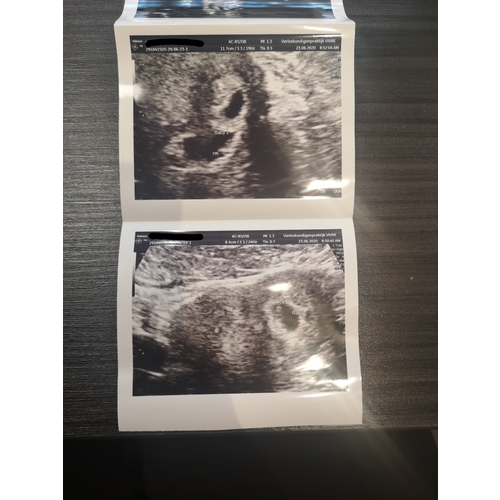

Bij mijn zijn het er ook twee! Vandaag 2e echo gehad met 8 weken en ziet er goed uit! Ze denken aan een twee-eiige tweeling bij mij, maar de gynaecoloog kon dit nog niet met zekerheid zeggen! 22 juli krijg ik mijn termijn echo met 11 weken en dan weten we meer!

Ja hier ook een tweeling op komst! De verloskundige zag met 8 wkn geen vliesje tussen de kindjes. Heel spannend, maar de gynaecoloog wel gelukkig! Het hoeft dus geen dik tussenschot te zijn. Met zo’n dun vliesje is het sowieso eeneiig. Maar het vliesje neemt wel risico’s weg! Nu wel elke 2 wkn een echo :)